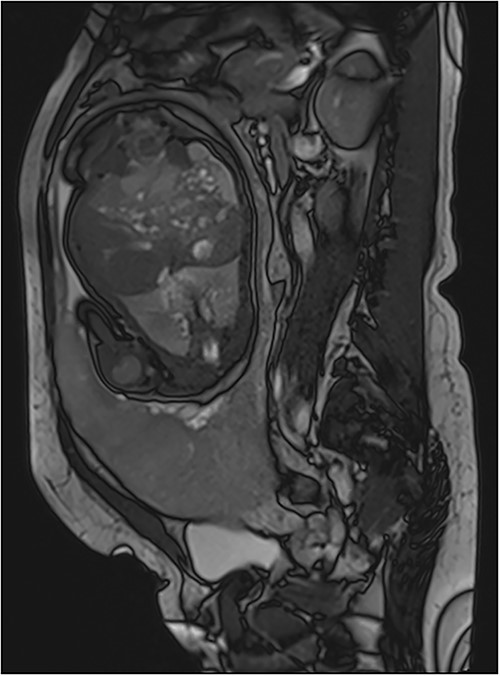

Diffusion weighted images can also be used to better see contours of the placenta [6]. It is important to note that MRI must be performed early enough to be able to plan childbirth and in order to decrease the false-positives (physiological placental changes at the end of pregnancy). Alamo et al. suggested performing it before 35 weeks of pregnancy while Lim et al. proposed before 30 weeks [7, 8]. Normal MRI signal of the placenta during at the end of 2nd trimester is a homogeneous isosignal aspect respecting the myometrium on T2-WI. As for the 3rd trimester, the placenta begins to have a more T2 hyposignal lobular and heterogeneous aspect. The myometrium usually has high signal on T2-WI (Fig. 4) with a trilaminar appearance.

Sagittal T2 Weighted Images showing normal MRI signal of the placenta and the myometrium at the end of 2nd trimester. Note the trilaminar aspect of the myometrium: retro placental layer in hyposignal (white arrow), intermediate layer (the zone of arcuate vessels in intermediate signal red asterisk) and the external layer (the serosa) with a thin T2 hyposignal aspect (blue arrow).